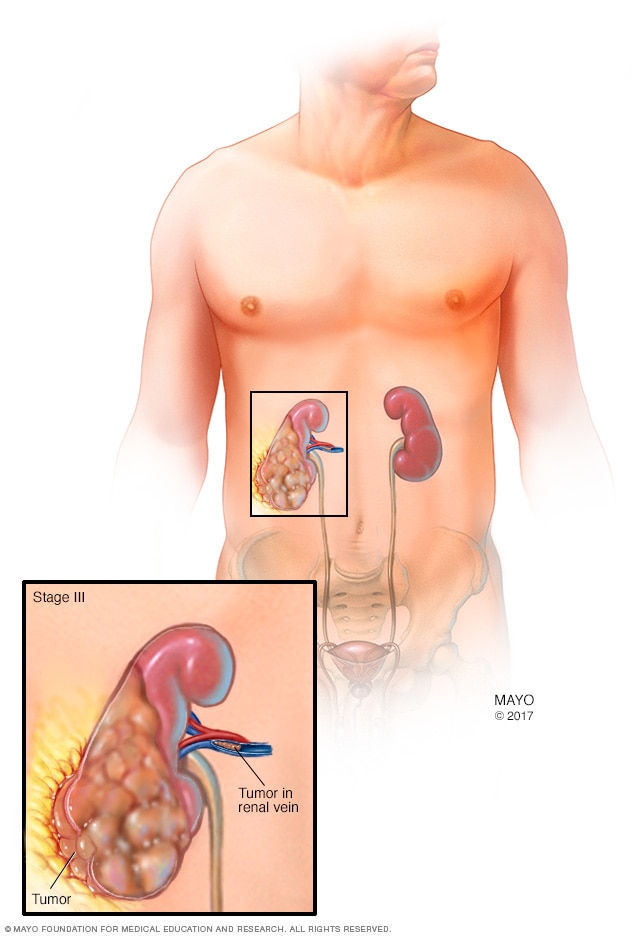

Stage 3 kidney cancer

A stage 3 kidney cancer may mean that the tumor in the kidney extends to the surrounding tissue. It also may mean that the cancer has spread to nearby lymph nodes.

The stages of kidney cancer range from 1 to 4. A stage 1 kidney cancer is small and confined to the kidney. As the cancer gets larger, the stages get higher. A stage 4 kidney cancer has grown beyond the kidney or spread to other parts of the body.